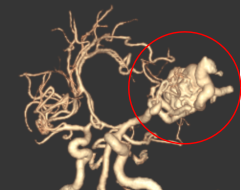

神经科急危重症诊治,尤其急性出血性、缺血性脑血管病及颅脑损伤抢救,脑血管病显微手术及介入诊疗(高血压脑出血显微镜/神经内镜下血肿清除术、急性脑血栓取栓术、脑动脉瘤栓塞术、脑血管畸形栓塞术、颅内动脉狭窄成形术、复合颈动脉斑块切除术、颈动脉及椎动脉狭窄支架置入术)。